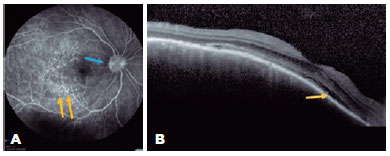

A 47-year-old woman was referred to our hospital for a follow-up of SO. She underwent complicated cataract surgery with retinal detachment in the left eye (OS) preceding the condition and was treated with dexamethasone 1 mg/mL eye drops in OU, brimonidine tartrate 2 mg/mL combined with timolol maleate 5 mg/mL bid in the OS, and prednisone 10 mg/day for 4 months. Ophthalmological examination revealed visual acuity (VA) of 20/20 in the right eye (OD) and luminous perception in the OS. Biomicroscopy revealed OD without changes, and in the OS, marked flare (3+/4+), without cells and bombé iris, was observed. The intraocular pressure was 18 mmHg in the OD, and the OS presented with hypotonia. Fundoscopy revealed a hyperemic optic disc and small SRD areas at the posterior pole that also involved the subfoveal region. FA revealed multiple pinpoints dispersed throughout the posterior pole (Figure 1A), and OCT revealed SRD (Figure 1B). The patient was followed up for 3 years, with gradual tapering of prednisone dosage until its suspension in 2015. OD fundoscopy demonstrated a "sunset glow fundus" appearance and Dalen–Fuchs nodules in the periphery; however, OS examination was impossible. The patient subsequently developed secondary glaucoma in the OD and was referred to a specialized service.